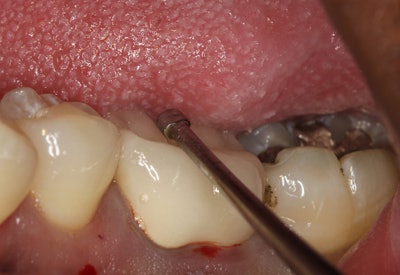

- Locate the crown occlusal interface. In most cases, the interface is located in the previous step, but, if not, the opening made in step 1 would have to be progressively enlarged until the cement seal becomes visible. Visual assistance devices such as surgical loupes or a microscope can be extremely helpful in this process. It is critical that you are working in the cement layer.

- Create a tunnel between the preparation's occlusal surface and the inner side of the crown (figure 6). Using a cylindrical bur (approximately 1.2 mm in diameter is recommended), an oval-shaped tunnel between the preparation's occlusal surface and the inner side of the crown is made. The difference in hardness between the dentin and the crown's structure will help the dentist ascertain the bur's position with regard to the dentine.

- Insert WAMkey into the tunnel and rotate with fingers to loosen the crown (figures 7 and 8). Simply insert the key all the way to the end of the tunnel drilled in step 3 and rotate it with a quarter turn with your fingers. If the tunnel was properly drilled, this movement should occur in the long axis of the preparation. Once the crown or bridge is removed (figure 9), it can be used as a temporary or placed permanently if so desired.